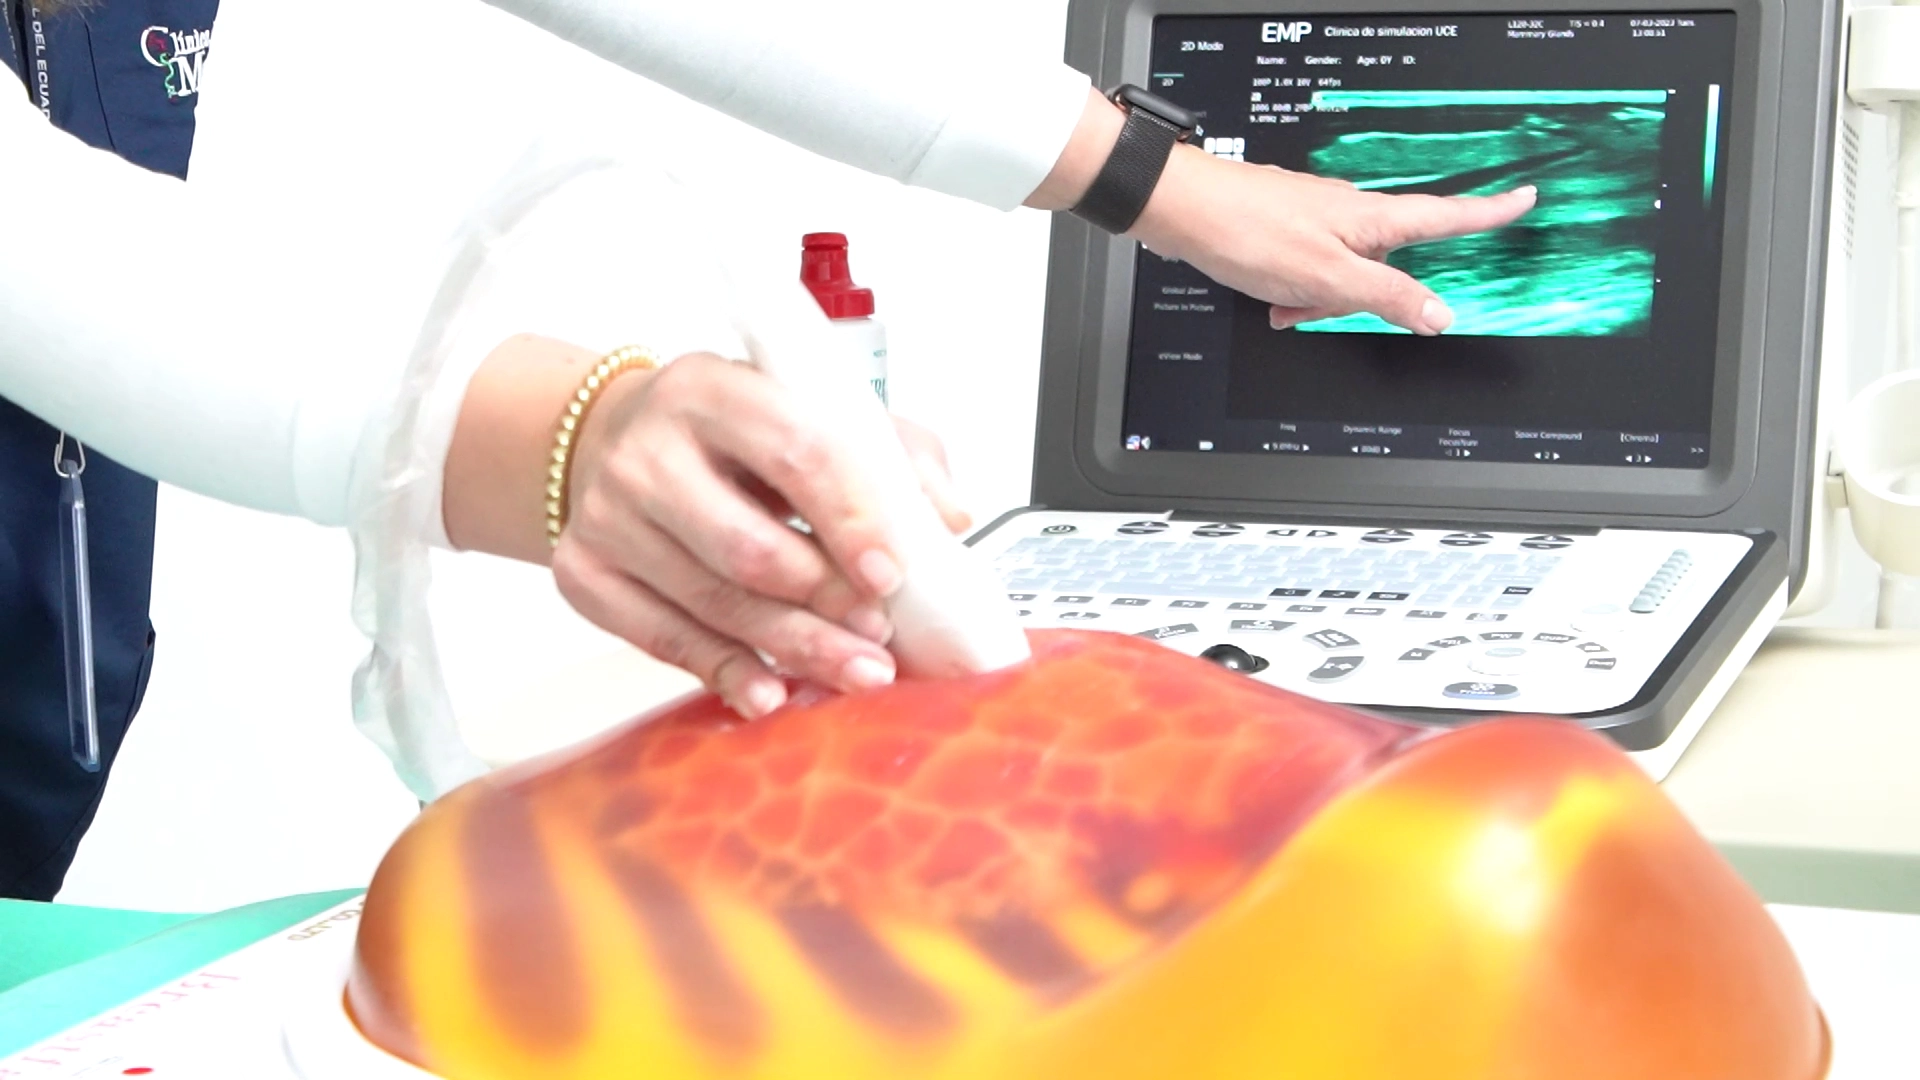

Simuladores de ecografía (ultrasound phantoms)

Modelos anatómicos realistas compatibles con equipos reales de ultrasonido. Incluyen simuladores de abdomen, pélvico, tiroides, vascular periférico y transvaginal, ideales para entrenamiento diagnóstico y guiado por imagen.